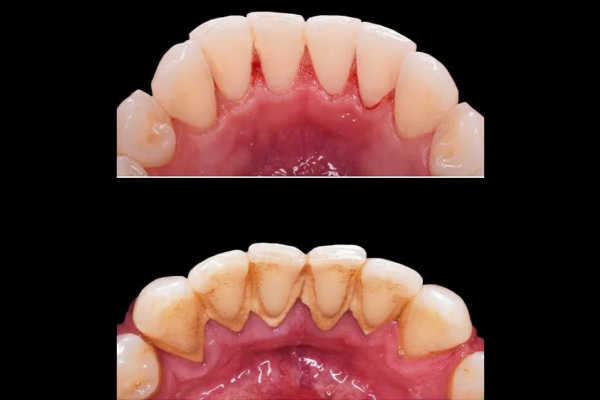

Gum disease, also known as periodontal disease, occurs when plaque and tartar build up along the gumline, leading to infection and inflammation. It begins as gingivitis, a mild form of gum disease that causes swollen, red gums that may bleed during brushing or flossing. If left untreated, it can progress to periodontitis, a more serious condition that can cause gum recession, bone loss, and even tooth loss.

We provide scaling and root planing (deep cleaning) to remove plaque and tartar buildup, helping to stop the progression of gum disease and promote healing.